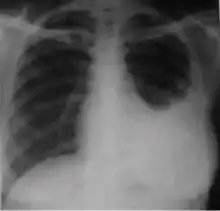

Chest x-ray showing dense opacity pleural effusion in the lower left lung of primary pulmonary TB.

4. Pleural effusion - Presence of a significant amount of fluid within the pleural space. This finding must be distinguished from blunting of the costophrenic angle, which may or may not represent a small amount of fluid within the pleural space (except in children when even minor blunting must be considered a finding that can suggest active TB).